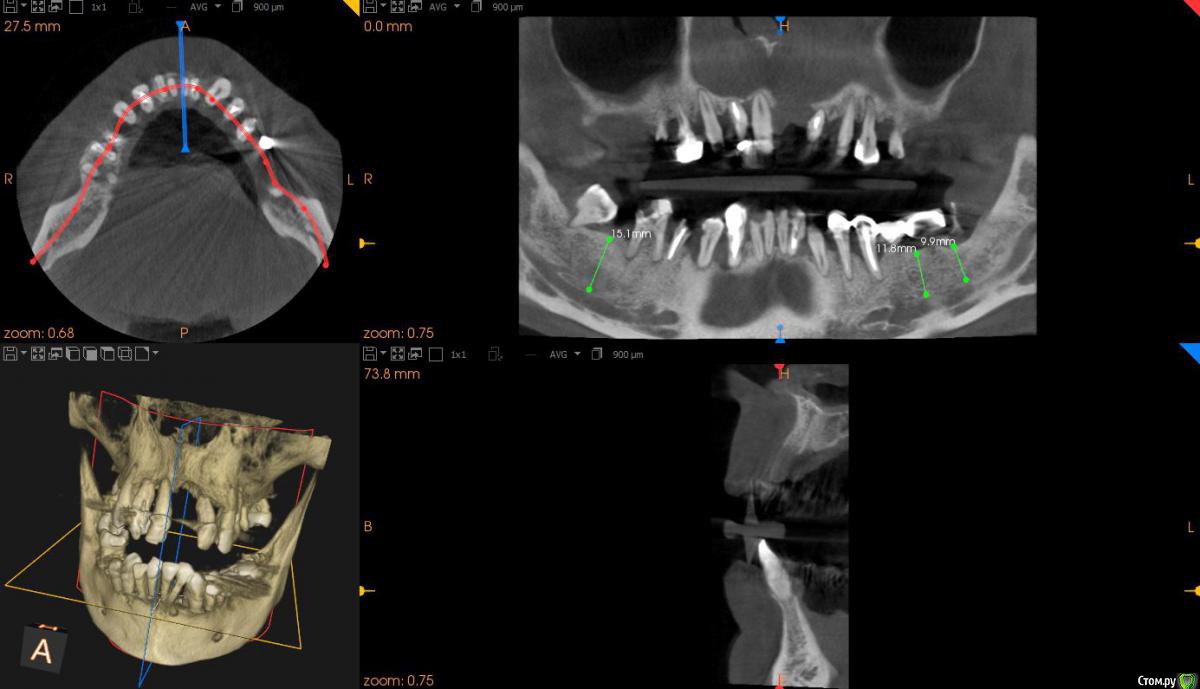

JurJul Опубликовано 17 апреля, 2018 Поделиться Опубликовано 17 апреля, 2018 Не знаю, возможно мой случай в раздел протезирования и не подходит, возможно нужна хирургия и имплантация. История. Живу в Белоруссии. В 2000 году сделал всё, что нужно было: мосты, коронки, виниры на передние зубы. На то время по высокому уровню стоматологии. Где-то через 2 года обнаружили онкологию (семенома) на 1 стадии. Операция, химия, лучевая. Препараты на химиотерапии этопозид, цисплатин. Всё благополучно прошло. Потом где-то через 2-3 года мосты и коронки стали беспокоить и постепенно они снялись. В начале 10-х годов был на нескольких консультациях - сказали, что у меня 2 варианта: ждать пока само всё выпадет и потом ставить всё полностью съемное "под Карегу" и второй вариант - удалять всё раньше и опять же ставить полностью под Карегу. Я как-то не могу с этим смириться, всё же думаю, что возможны варианты ещё, тем более, что научно-технический как и медицина со своими технологиями двигаются семимильными шагами. Про импланты мне говорили, что в моём случае ничего не будет стоять, т.к. была в прошлом химия и лучевая и у меня всё подвижно, что собственно подтверждается состоянием зубов и корней, которые норовят выходить сами. Были частые воспаления дёсен и признаки пародонтоза. В последние месяцы стали шататься передние верхние, прямо похоже как у детей, когда зубы меняются... И вот совсем недавно выпал (помог ему немного) верхний 1-ца. Бисфосфонаты не принимал. Зубы после онко удалял. Лунки заживали нормально.В субботу 14.04 был на консультации у имплантолога. Ведущий специалист в этой области в РБ... во всяком случае так его позиционирует Гугл )) Так вот мне сразу был предложен самый оптимальный в моём случае вариант - всё на 6 на обе челюсти и всё сразу и быстро. Удаляем всё и сразу и тут же вкручиваем импланты (Израиль или Нобель). Через 5-7 дней ставим временный несъемный протез и через полгода вуаля постоянный несъемный (либо керамику либо цирконий по желанию). Типа это в моём случае самое оптимальное и не очень тяжёлое в физическом и психологическом плане (сразу с зубами, не нужно съёмный протез полгода носить или без зубов долго ходить )... Я, честно говоря, не готов на такой вариант... Я понимаю, что возможно хороших зубов, которые смогут служить опорой под мост/ы, может и нет. И, возможно, и нужно будет всё удалить... Но я думаю, может и ошибаюсь, что есть и др. методы имплантации, если это неизбежно. Как мне сказали на консультации, что предложенный вариант единственный для верхней челюсти, варианты могут быть по низу, но по верху - без вариантов...Озвучена по стоимости работа "под ключ" : с израильскими имплантами 12 тыс. дол. , с американскими 20 тыс. дол. Дело даже не в стоимости. Просто мне не хотелось бы стать одним из авторов стом. форумов с мольбой о помощи в исправлении чьей-то работы с имеющимися проблемами. Больше всего на свете я не хочу проблем и переделок. Я понимаю, что на 100% нельзя быть уверенным в результате, но минимизировать риски, выбрав самый лучший или оптимальный вариант, можно. Вот поэтому я решил обратиться сюда за консультацией. Ссылка на 3D томографию: https://drive.google.com/open?id=1puDkkPZG_C-UQCklhUjX5sdAS_SOIooZВзываю к помощи товарищей врачей! Только на вас уповаю Ссылка на комментарий

St. Опубликовано 17 апреля, 2018 Поделиться Опубликовано 17 апреля, 2018 Обзорные срезы ( верх, низ, топография нижнечелюстного нерва), дефект в обл 21 Ссылка на комментарий

kozloff Опубликовано 18 апреля, 2018 Поделиться Опубликовано 18 апреля, 2018 План действий.Удаление зубов.Повторное КТ.Рекомендуется костная пластика.Имплантация по шаблону. Ссылка на комментарий